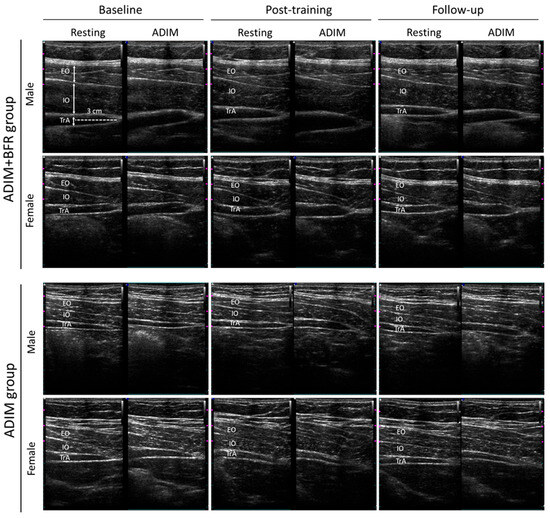

2.3.2. Ultrasound Image Analysis

3.2. Alternations in Muscle Thickness at Baseline, Post-Training, and at Follow-Up

3.3. Contraction Ratio, Contraction Difference, and Preferential Activation Ratio